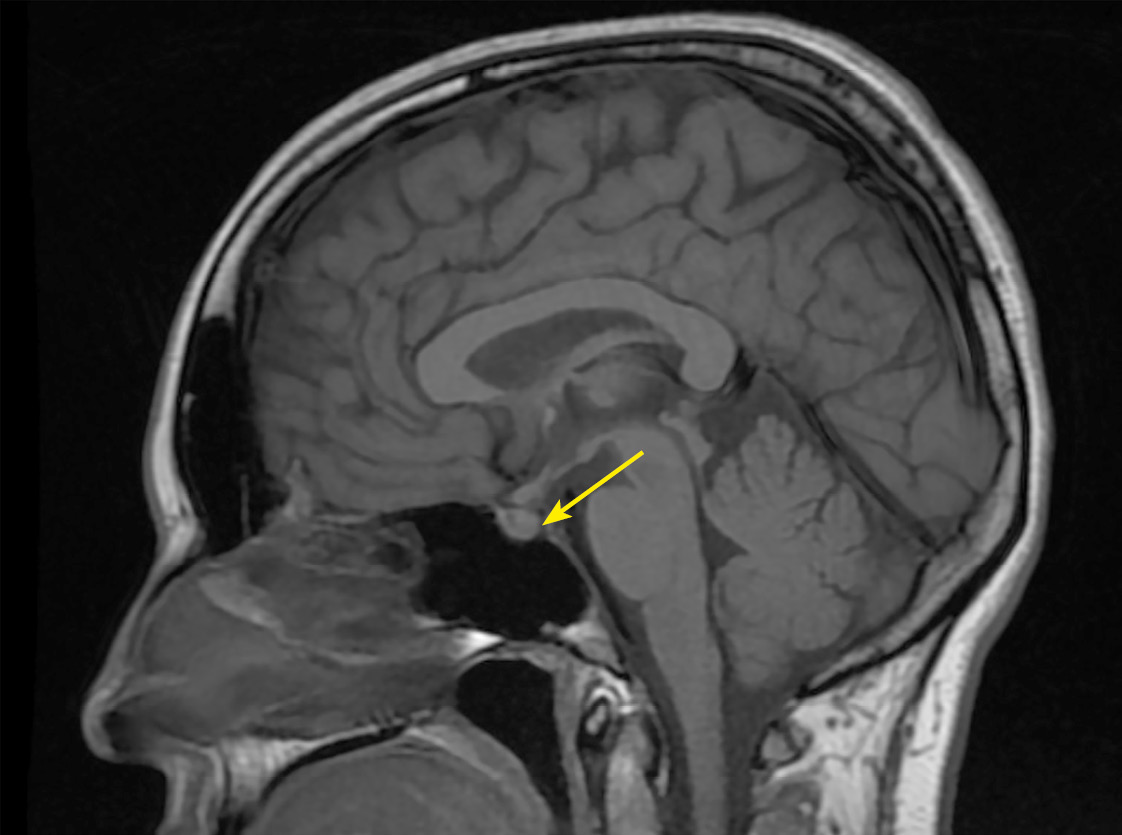

В рамках обследования по поводу головных болей и нарушения полей зрения на 17–18 неделе беременности пациентке выполнена МРТ головного мозга без контрастного усиления, по результатам которой выявлены признаки аденомы гипофиза размерами 10x15x20 мм с супраселлярным ростом и умеренной компрессией хиазмы, нейрогипофиз не дифференцировался (рис. 1, 2).

Рисунок 1. МРТ головы без контрастного усиления, Т2-взвешенное изображение,

коронарная (фронтальная) проекция.

МР-картина «аденомы» гипофиза размерами 10x15x20 мм

с супраселлярным ростом и умеренной компрессией хиазмы (изменения указаны стрелкой).